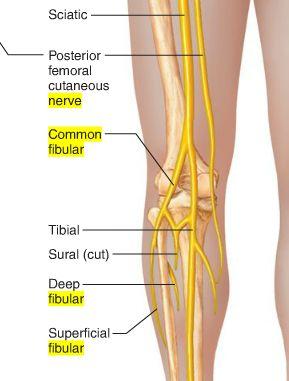

Into which two nerves does the sciatic nerve bifurcate?

tibial and common fibular

The common fibular nerve is formed from ventral rami from spinal cord levels _______

L4 - S2

The common fibular nerve is the (lateral/medial) division of the sciatic nerve

lateral

Describe the pathway of the common fibular nerve

wraps around the neck of the fibula

bifurcates into deep and superficial fibular nerves

What muscle does the common fibular division of sciatic nerve innervate?

ONLY biceps femoris short head

To which nerve might there be damage if a patient is suffering from foot drop?

common fibular nerve

What would be the consequences if the common fibular nerve was completely severed?

Patient would be unable to evert foot

numbness on dorsum of foot

unable to doriflex or extend digits of foot

The superficial fibular nerve is the (lateral/medial) branch of the ________

lateral; common fibular nerve

which muscles does the superficial fibular nerve innervate?

both lateral leg muscles (fibularis longus and fibularis brevis)

The deep fibular nerve is the (medial/lateral) division of the _________-

medial; common fibular nerve

What is the path of the deep fibular nerve?

travels between tibialis anterior and extensor hallucis longus

continues onto the dorsum of the foot for sensory innervation in the flip flop area

What is the pathway of the superficial fibular nerve?

runs between fibularis longus and fibularis brevis

continues onto the dorsum of the foot

Which muscles does the deep fibular nerve innervate?

innervates all anterior leg muscles (extensor hallucis longus, extensor digitorum longus, tibialis anterior, and fibularis tertius) and both muscles of the dorsum of the foot (extensor digitorum brevis, extensor hallucis brevis)

O C D of common fibular nerve

O sciatic nerve

C forms as sciatic nerve bifurcates at apex of popliteal fossa. follows medial border of biceps femoris with its tendon. passes over posterior aspect of head of fibula then winds around neck of fibula deep into fibularis longus where it divides into deep and superficial fibular nerves

D knee joint via articular branch and lateral aspect of posterior leg via sural cutaneous nerve

(common fibular branch of sciatic nerve innervates short head of biceps femoris)

OCD of superficial fibular nerve

O common fibular nerve

C arises between fibularis longus and neck of fibula. descends into lateral compartment of leg; pierces deep fascia at distal third of leg to become subcutaneous

D fibularis longus and brevis. medial dorsal cutaneous n, intermediate dorsal cutaneous n

OCD of deep fibular nerve

O common fibular nerve

C arises between fibularis longus and neck of fibula; passes through extensor digitorum longus and descends on interosseous membrane. crosses distal end of tibia and enters dorsum of foot.

D tibialis anterior, extensors digitorum brevis and longus, extensor hallucis brevis and longus, and fibularis tertius. lateral cutaneous of big toes, medial cutaneous of second toe.